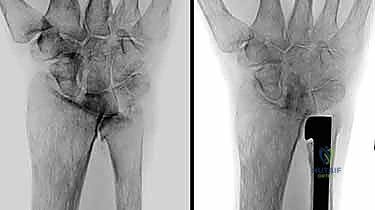

2. التصوير بالأشعة السينية (X-rays)

تُعد الأشعة السينية الخطوة الأولى والأساسية. توضح التآكل الغضروفي، وتكّون النتوءات العظمية، والتغيرات في محاذاة العظام. يقوم الدكتور هطيف بطلب صور في وضعيات محددة (أثناء الكب والاستلقاء) لتقييم الديناميكية الحركية.

مرض مناعي ذاتي يهاجم الغشاء الزلالي المبطن للمفاصل. مفصل الزند والكعبرة البعيد هو أحد الأهداف الشائعة لهذا المرض، مما يؤدي إلى تدمير سريع للغضاريف والعظام والأربطة المحيطة، وينتج عنه تشوه وعدم استقرار شديد (غالبًا ما يظهر كبروز ملحوظ لرأس الزند في ظهر الرسغ).

3. الصدمات والكسور المعقدة

الكسور التي تصيب أسفل الكعبرة أو الزند (مثل كسر كوليس أو كسر جاليازي) إذا لم تلتئم بشكل صحيح، يمكن أن تغير الميكانيكا الحيوية للمفصل، مما يؤدي إلى تآكل سريع (التهاب المفاصل ما بعد الصدمة).